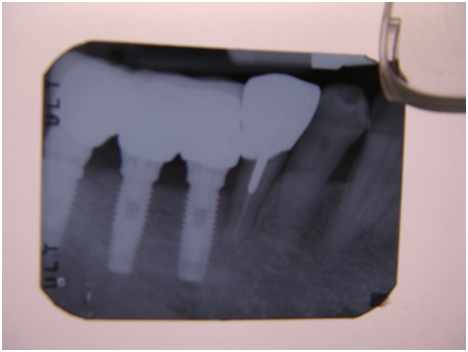

和患者積極溝通,由於患者神經管上的骨高度並不理想,建議積極移除中間兩顆有問題的植體重放,阻止發炎與骨破壞繼續下降;但患者想再追蹤。

患者於99/10期間因起床後有暈倒現象,住院後持續吃抗凝血劑,雖有發炎但不致於不舒服,因此一直不願積極處理;終於在100/03/1將兩顆植體移除,並於100/05/23回診評估再次植牙的條件。

100/05/23

於100/06/07重新放置兩顆植體

並於100/10/25將中間兩顆植體做二階接出

由於前後植體的高低差距太大,決定將中間兩顆高度較為一致的植體假牙做連結,但前後兩顆做單顆假牙的設計。

100/11/21 補綴完成

目前植體周圍的組織都很理想健康並追蹤中。

a. 右下第一小臼齒的植體位置,放置得太低;若能將此顆植體上的polished surface放在骨平面上,應可減少之後將鄰近植體骨高度往下帶的情形。

b. 近遠心間距在植體間的間距需求為2-3 mm(指最終第一小臼齒植體與鄰近植體間距),比當初第一小臼齒尚未拔除時,是自然牙與植體的間距需求更大(最少為1.5mm);因此造成骨破壞的因素之一,也可能和鄰近植體的間距不足有關。